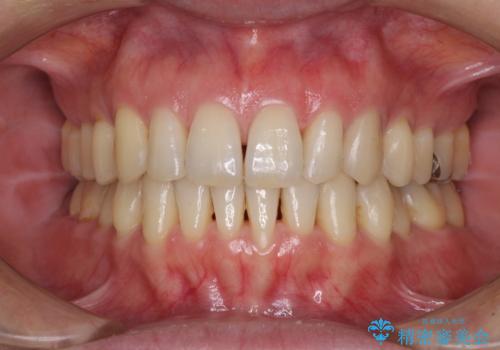

急速拡大とワイヤー抜歯矯正で唇を閉じやすく

- 口元の突出感を気にして来院された患者様です。

デコボコと口元の突出感が認められたため、上下左右の第1小臼歯4本を抜歯してのワイヤー矯正を行うこととしました。

上顎歯列幅を拡大したことで、デコボコを容易に解消することができるようになったため、抜歯により得られたスペースを口元の突出感改善に利用することができました。